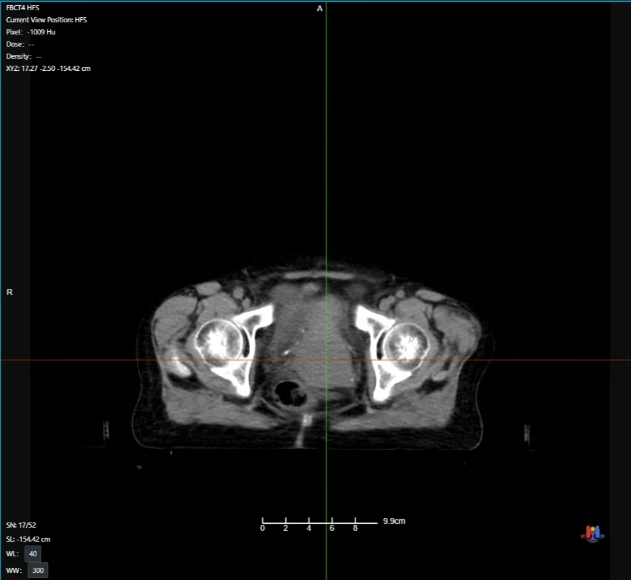

放疗中期病灶影像

整个放疗治疗周期中刘阿姨反馈为基本无无明显不适。通过治疗期间CT影像可发现,随着放疗次数增加病灶逐步减小,效果明显,最终该病灶基本消失!